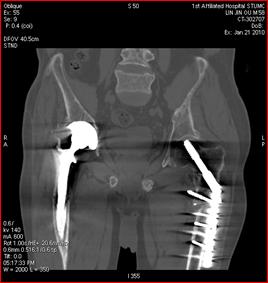

高能量X射线可以去除高密度金属引起的伪影

常规CT 宝石能谱CT

140keV能量成像可以除去金属引起的伪影,更加清晰观察术后情况